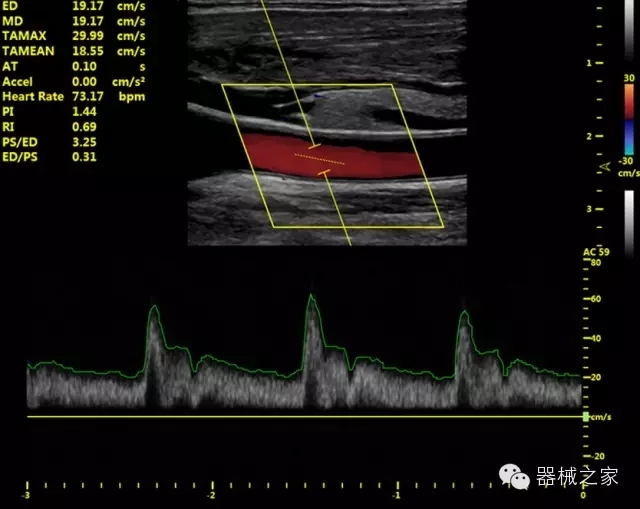

·獨有的HoloTM PW 實時3取樣門PW成像技術(shù),精確進(jìn)行血管診斷;

·一鍵優(yōu)化B、Color、PW,Auto Doppler自動識別血管位置、偏轉(zhuǎn)角度等,提高工作效率;

·30°超廣角精細(xì)偏轉(zhuǎn)成像技術(shù),更優(yōu)異的頻譜圖像;